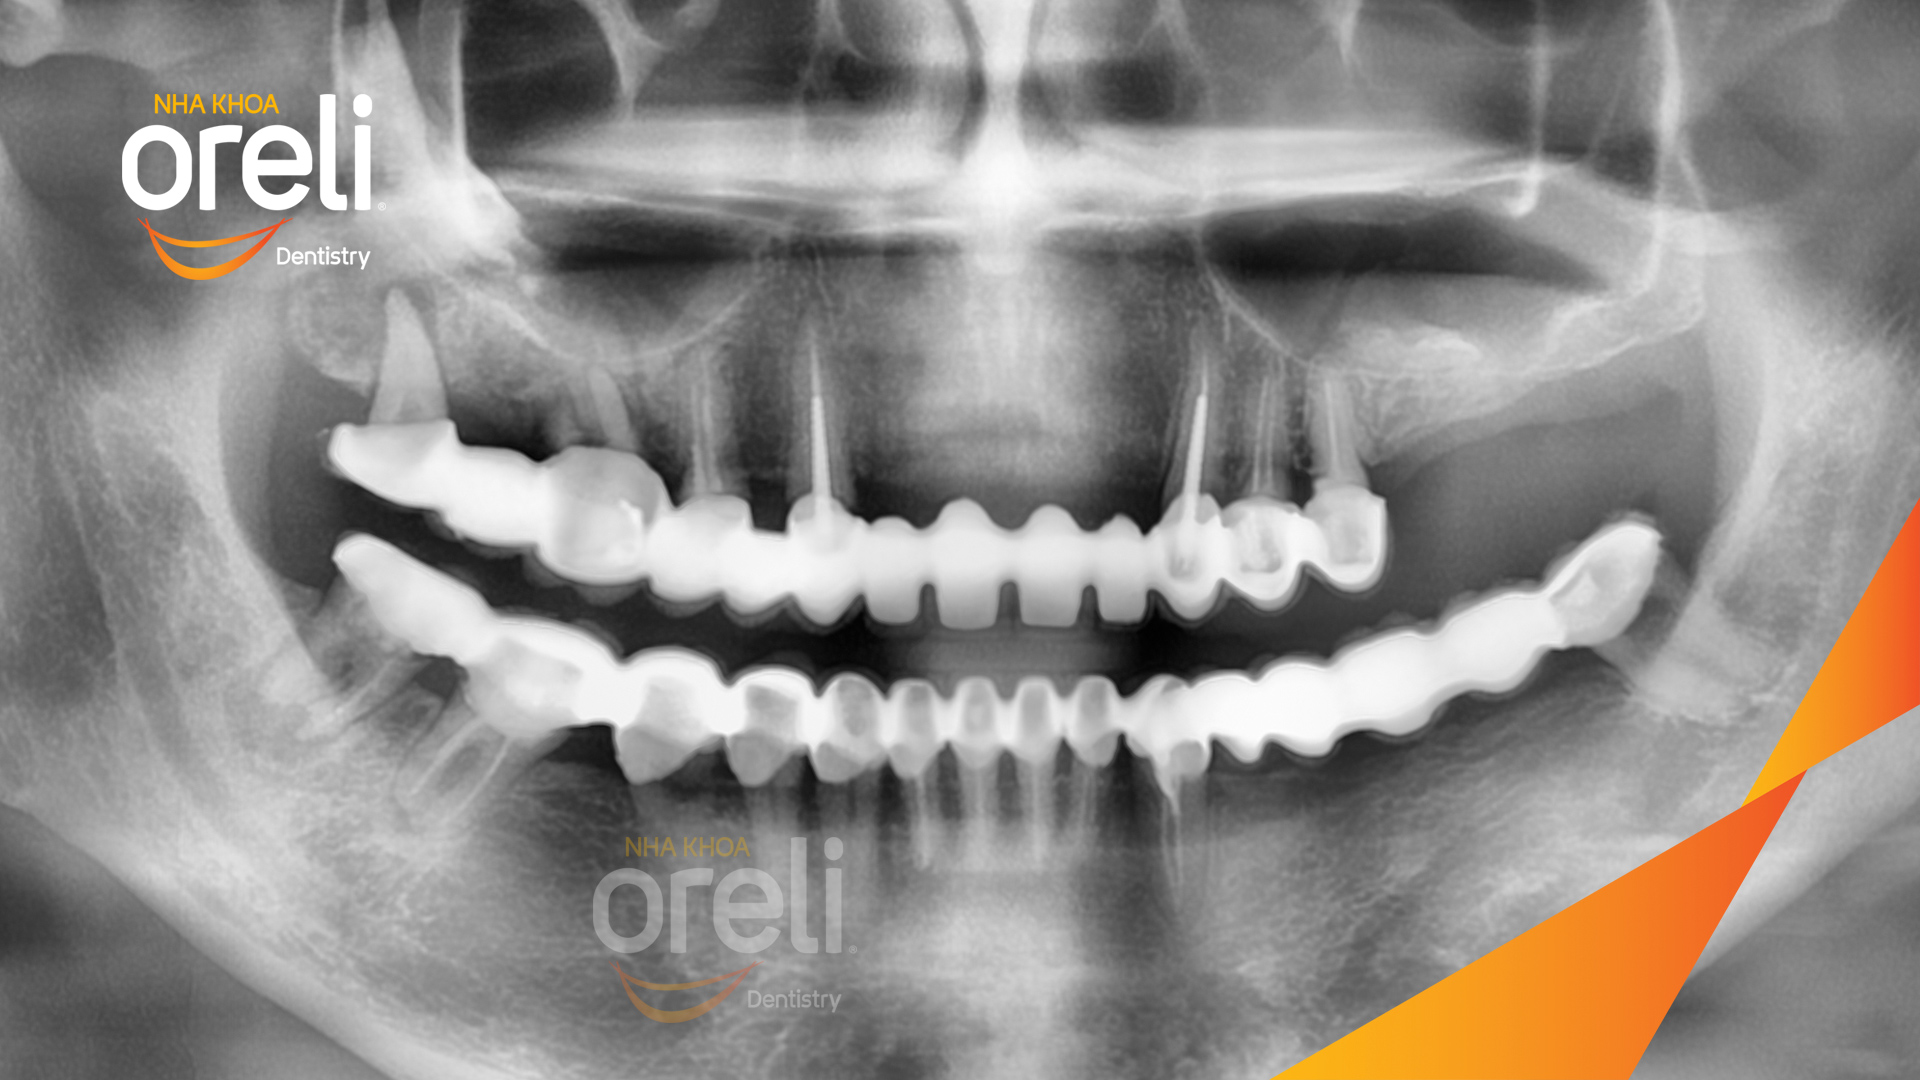

Ca trồng răng implant hàm trên và ba răng hàm dưới hình ảnh trước sau

Ca trồng răng implant toàn hàm phục hồi ăn nhai và thẩm mỹ nụ cười. Kết quả thực tế trước và sau điều trị tại Nha khoa Oreli.

Tình trạng: Cầu răng sứ hàm trên lung lay, các chân răng cũ tiêu xương

Hình ảnh thực tế